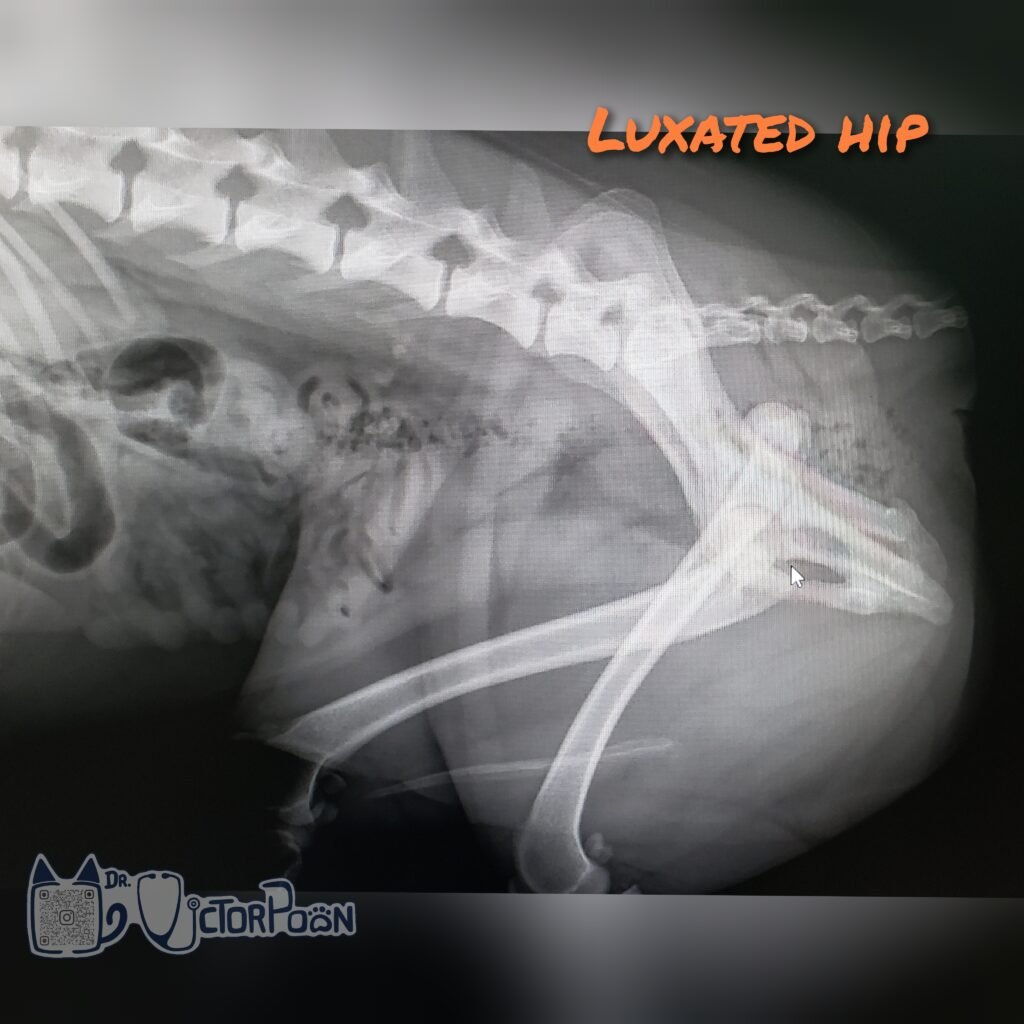

Surgical options should be considered for chronic hip luxation and hips that reluxate after closed reduction. The 2 main types of procedure include round ligament reconstruction (Toggle Pin technique) and salvage procedures (femoral head and neck excision [FHNE] or Total hip replacement [THR]). Each procedures have their pros/cons, and should be discussed prior to surgical intervention.

Some of the factors for consideration include: Clinical signs, Weight and size, Age, Cost and Hip conformation.